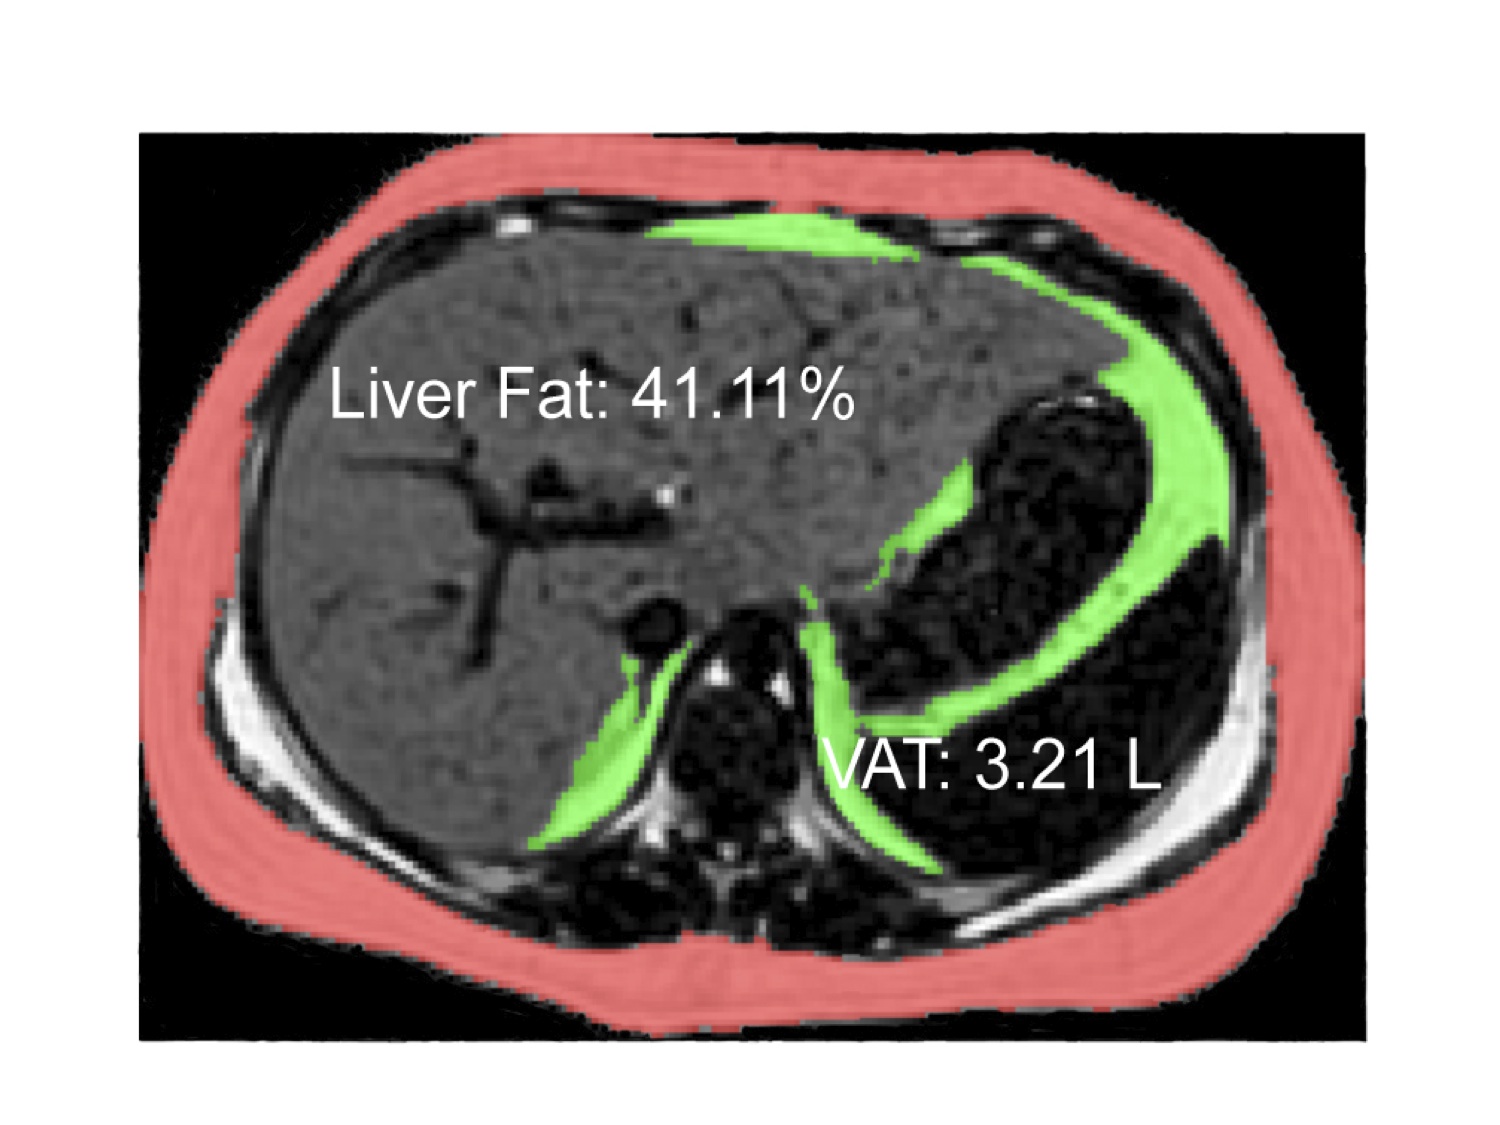

NAFLD is the most common cause of fatty liver disease in the U.S., serving as a precursor to non-alcoholic steatohepatitis, which can lead to cirrhosis, permanent liver damage and liver cancer. Adding insult to injury, NAFLD is also associated with the development of type 2 diabetes and influenced by genetics. Multiple studies have shown that Hispanics are genetically predisposed to fatty liver disease with a recent study identifying the PNPLA3 gene, which is linked with over 2-fold higher liver fat content. Almost 50% of Hispanics carry this gene as opposed to around 20% of other populations. Furthermore, the impact of this gene is manifested in children as young as 8 years of age.

Complicating matters is new evidence of a gene-diet interaction in Hispanics wherein higher liver fat is linked with higher sugar intake in subjects carrying a specific variant of the PNLPA3 gene. Thus, Hispanics carrying the PNPLA3 variant coupled with a high sugar diet (specifically high fructose which is a substrate for conversion to fat in the liver) are particularly susceptible to increased liver fat and subsequent disease.

With a genetic tendency to deposit fat in the liver, an increasingly high sugar diet(namely fructose), and a rapid rise in childhood obesity, the Hispanic population in particular is highly vulnerable to fatty liver disease. A variety of public health measures are required to address this issue.